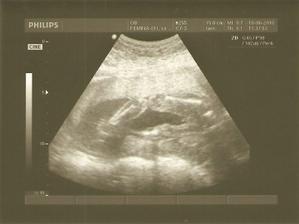

12.7.2010 - nooo a tento den si zapamätáme asi navždy, ideme na 4D a uvidíme drobca, že ako vyzerá .... takže 3D je za nami a malý vyzerá, že bude po svojich rodičoch, taký malý hanblivec....alebo len chce aby sme boli prekvapení že aký bude kráásny...ale on je kráásny aj na tých našich fotkách....pekne počúva čo hovorí aj pán doktor a aj maminka s ocinkom....sme radi že ho máme a tento den bude den ked sme videli nášho drobca skoro ako na živo ;o))